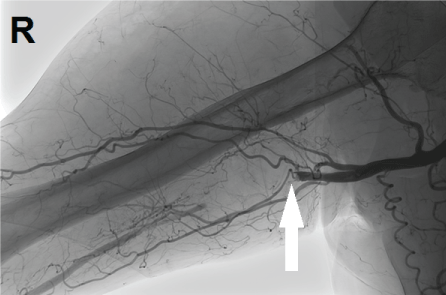

A seventy one-year-old man was presented to the emergency department in October 2016. He was working on the farm of his son when he got trapped between hydraulic closing doors of a truck. He sustained trauma to his head and to his right arm. His medical history consisted of a transient ischemic attack and chronic obstructive pulmonary disease (GOLD classification 2). He was using pulmonary medication and a combination of carbaspirin calcium (100 mg once a day) and dipyridamole (200 mg twice a day). Trauma care was conform advanced trauma life support principles. Initial presentation showed a hemodynamically stable patient with full consciousness with a laceration of his head and bruising to the right arm. The X-ray imaging of thorax and pelvis, the focussed assessment with sonography for trauma, blood analyses and electrocardiogram were normal. A secondary survey showed a laceration on the medial aspect of the right upper arm with bruising and swelling. The capillary refill of his right arm was delayed and peripheral pulses were absent. A pulse oximetry measurement on the right index finger showed 95% saturation. The arterial pressure on the right could not be measured and on the left measured 144/72 millimetres of mercury. His right arm had diminished motoric functioning and sensibility was severely impaired. A regular X-ray of his right arm showed no fractures but did show air configurations in the subcutaneous tissue (Figure 1). An additional computed tomography of cerebrum and cervical vertebrae showed no abnormalities. In the same session a CT-angiography of the right arm was performed. The Ct showed subcutaneous air surrounding the brachial artery with a dissection and segmental thrombosis (Figure 2 and Figure 3). The neurologist made a careful neurological examination while the trauma surgeon cleared the patient for the operation. Directly after the trauma resuscitation he was brought to the hybrid operation room to perform surgery. General anaesthesia was given to the patient to facilitate a direct conversion to open surgery if necessary. A sterile exposure was made for both groins and the right arm and cervical area. A duplex ultrasound guided retrograde puncture of the right common femoral artery and placement of a 6 French sheath gave access. After gaining arterial access systemic heparin was administered (5000 international units). With a Terumo guidewire (0.035") [Terumo Europe NV, Belgium] and a SIM1 catheter [Cordis Corporation, USA] the axillary artery was reached through the brachiocephalic trunk. A digital subtraction angiography showed a traumatic dissection of the proximal brachial artery (Figure 4). In a gentle twisting fashion the 0.035 guide wire was advanced through the lesion follow by the catheter. An angiography through the catheter, distal to the lesion, confirmed intraluminal positioning of the catheter. After this recanalization the SIM1 catheter was exchanges for a Multi-purpose catheter [Cordis Corporation, USA]. A smaller guidewire (0.018") was placed and a 6 mm balloon angioplasty was performed. After angioplasty two 5 mm × 100 mm Supera [Abbot, USA] stent grafts were deployed in telescopic fashion with the distal stent being deployed first (Figure 5). The control angiography showed a good positioning of the stent grafts (Figure 6). The puncture site was closed with a Star close closure device [Abbot, USA]. After surgery distal pulsations at the wrist had restored and the sensory impairment was recovering. During the first 2 post-operative days the motoric disability markedly improved to nearly normal. Postoperative recovery was without complications. Patient received dual platelet anticoagulation (carbasparin calcium 100 mg once a day and clopidogrel 75 mg once a day) for the first 3 months. After three months his own pre-trauma anticoagulation therapy was restarted (carbaspirin calcium and dipyridamole). A control CT-angiography at 4 months post-operatively showed patent stent grafts with good deployment. Duplex-ultrasound imaging of the stent grafts showed patent stents at 6 months follow up. Unfortunately the patient did sustain concomitant neurological damage to the brachial nerves plexus at trauma. At 4 months post-operatively the neurosurgeon planned a decompression of the ulnar nerve. To date nearly all motoric functioning of his arm recovered except for fine motoric functioning.

Figure 4: Traumatic dissection of right arteria brachialis. View Figure 4